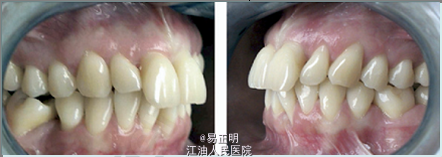

主述:上切牙凸出 女,22岁,无系统病史,有正畸史(14岁时,拔除了下颌两颗第一前磨牙)

前牙覆HE6mm,覆盖5mm;磨牙Ⅲ类关系;尖牙Ⅱ类关系;上下颌前牙区牙龈退缩;几乎全牙列都有深牙周袋,其中上下颌切牙处最深;探诊出血;患者有磨牙习惯。 上下中切牙和第一磨牙有明显的垂直性骨吸收,牙周医师诊断为侵袭性牙周炎

诊断:侵袭性牙周炎,牙列拥挤 矫治目标: 1.消除HE创伤 2.排齐牙列,便于清洁口腔 3.重建颜面美观